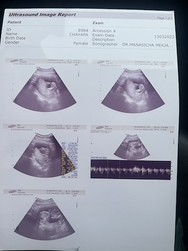

ตอนนี้ได้15+1 week อีก1วันไปหาคุณหมอ มีเเม่ๆคนไหน ยะระใกล้ๆกันละซาวเห็นเพศไหมคะ💞

ถ้าน้องอยู่ในท่าอ้าขาจะเห็นไวค่ะแม่ ของเรา14+3 w.น้องอ้าขาหมอบอกว่าน่าจะ..ผุ้หญิง

14+4 w ของเราเห็นเป็นกระจู๋ แต่หมอบอกว่าให้ชัวตอน5เดือน

14วีค กองตูดให้ดู ญ ค่ะ

15. หมอไม่บอกเพศค่ะ